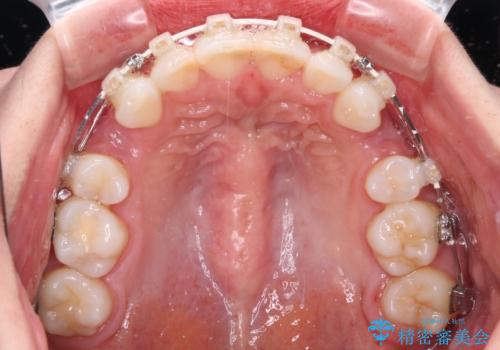

- 矯正装置

- 審美装置

- 口元の閉じにくさと、奥歯の咬み合わせを気にして来院された患者様です。

左下の大臼歯2本が顕著に舌側に傾斜しているため、まずは奥歯の咬み合わせを改善をし、その後上下左右の第1小臼歯4本を抜歯することで口元を引っ込めながら整えることとしました。

奥歯の咬み合わせ改善には1年ほどの期間と処置中の噛みにくさを強いることとなりましたが、抜歯後はスムーズに治療を完了させることができました。